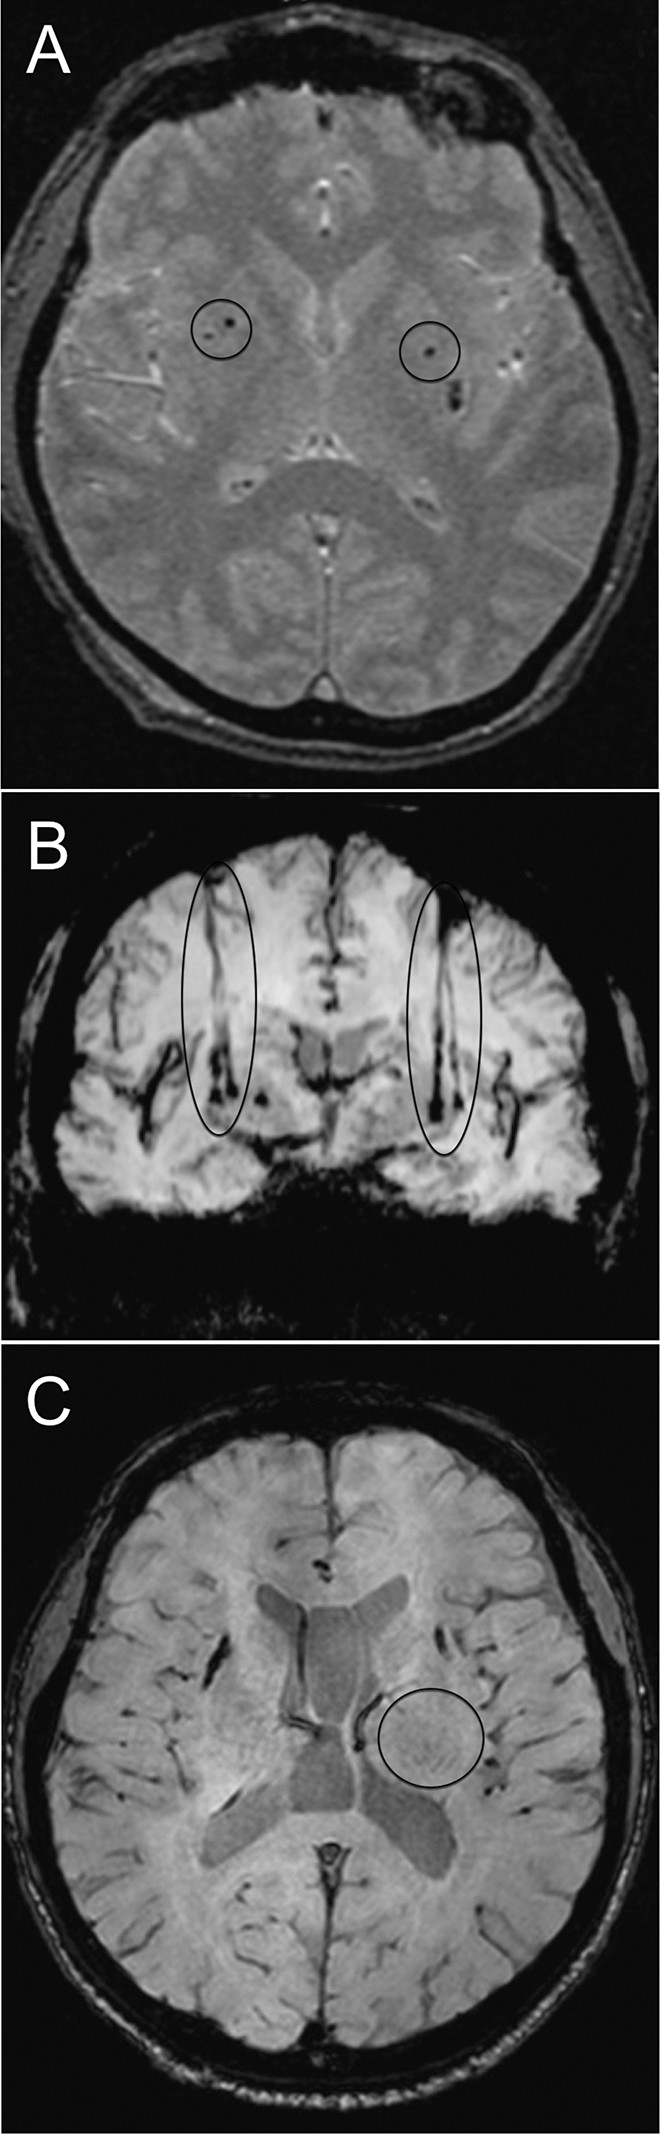

移植患者的代表性腦部 MR 圖像

如圖2所示。細胞植入的位點(diǎn)和軌跡路徑如圖 1 和 2 所示。分別參見(jiàn)圖 2A 和 2B。在1、2和4年隨訪(fǎng)的幾個(gè)針跡結束時(shí),在 T2 加權圖像上識別出小簇低信號。在 P4 的年度 MRI 監測中,在右側殼核(圖2C)中觀(guān)察到強大的移植物生長(cháng),沒(méi)有大腦結構的異常。未顯示腫瘤形成的證據。

圖2:移植患者的大腦MR圖像。